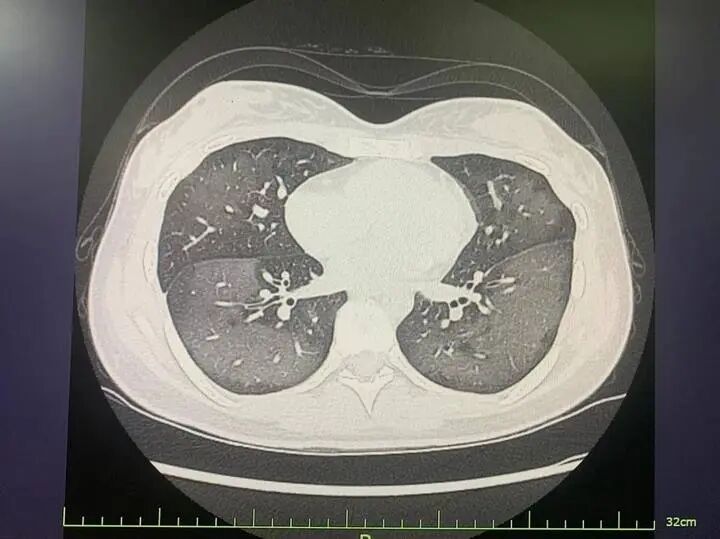

急診科童婭玲主治醫(yī)師接診了麗麗,經(jīng)CT檢查發(fā)現(xiàn),麗麗的雙肺呈現(xiàn)大范圍白色樣病變,報(bào)告提示“白肺”。

麗麗被診斷為“急性過(guò)敏性肺炎”,急診專家對(duì)麗麗給予吸氧、激素抗炎抗過(guò)敏等對(duì)癥支持處理后,急性癥狀得到緩解,她被收入呼吸內(nèi)科病房進(jìn)一步住院治療。

急診科主任陸遠(yuǎn)強(qiáng)主任醫(yī)師解釋,此類“白肺”與使用防曬噴霧時(shí)吸入的有害物質(zhì)有關(guān),噴霧中的某些化學(xué)成分會(huì)刺激誘發(fā)一系列過(guò)敏反應(yīng),從而導(dǎo)致廣泛的氣管、支氣管乃至肺水腫,讓肺部無(wú)法正常工作。

陸遠(yuǎn)強(qiáng)主任介紹,“白肺”是指在胸部X片或肺部CT等影像學(xué)檢查中,看到患者肺部呈現(xiàn)大范圍的白色陰影。